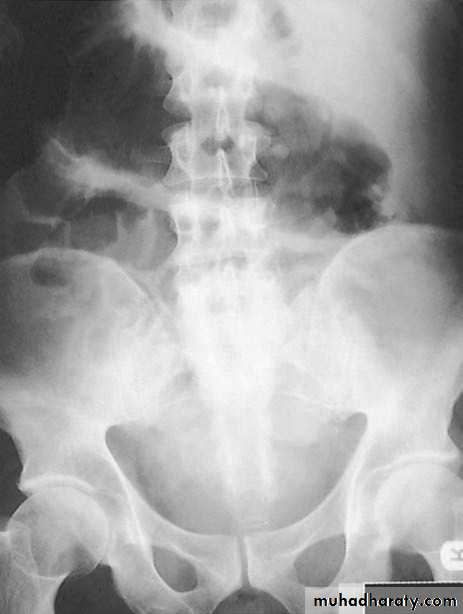

Plain x-ray

- Useful in toxic megacolon.transverse colon is dilated

large mucosal islands (edematous mucosal remnants between extensive ulcers).

No haustration